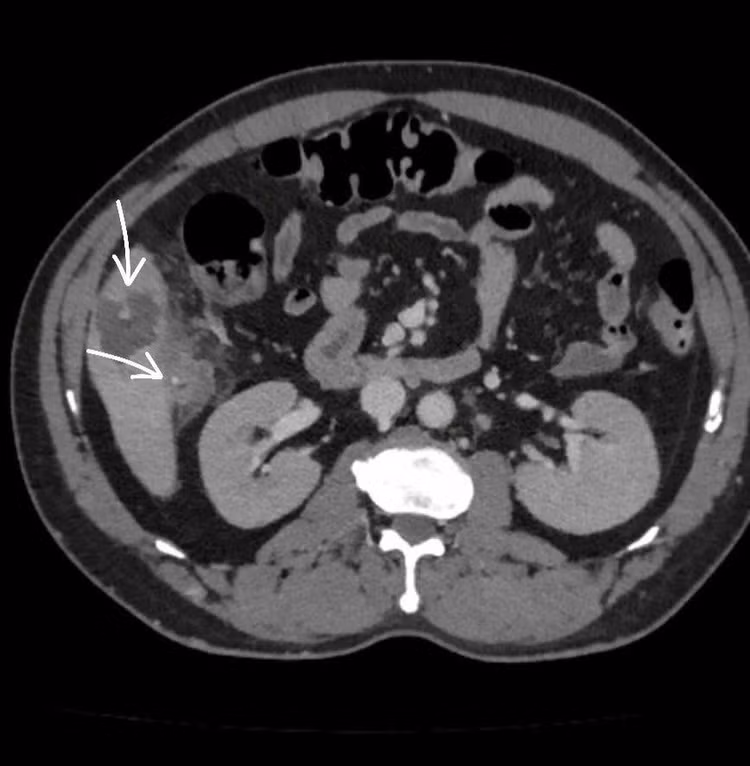

Hình ảnh mảnh xương nhỏ xuyên qua thành đại tràng tại góc gan, găm vào nhu mô gan hạ phân thùy V - Ảnh BVCC

Kết quả chẩn đoán hình ảnh (CT scan) cho thấy một mảnh xương nhỏ xuyên qua thành đại tràng tại góc gan, găm vào nhu mô gan hạ phân thùy V, tạo ổ áp xe kích thước 56x36mm, kèm viêm dày thành đại tràng vùng góc gan. Đây là nguyên nhân chính gây ra ổ nhiễm trùng nguy hiểm.